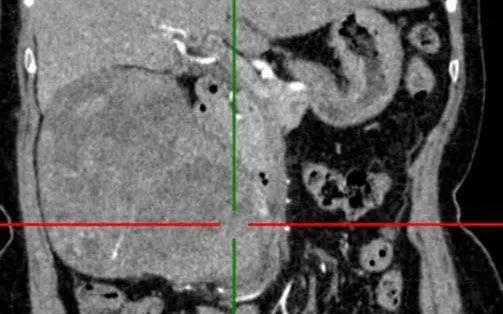

Thăm khám cho thấy bệnh nhân tỉnh táo, đau tức vùng mạn sườn và thắt lưng phải. Sờ thấy khối vùng mạn sườn phải mật độ chắc, ranh giới không rõ. Kết quả chụp cắt lớp vi tính bụng có tiêm thuốc cản quang ghi nhận thận phải to, nhu mô không đều, có khối choán chỗ ngấm thuốc mạnh kích thước khoảng 118 x 133 x 135 mm, đài bể thận giãn, không thấy sỏi. Bệnh nhân được chẩn đoán u thận phải. Một số thăm dò khác phát hiện viêm trực tràng và trĩ độ I.